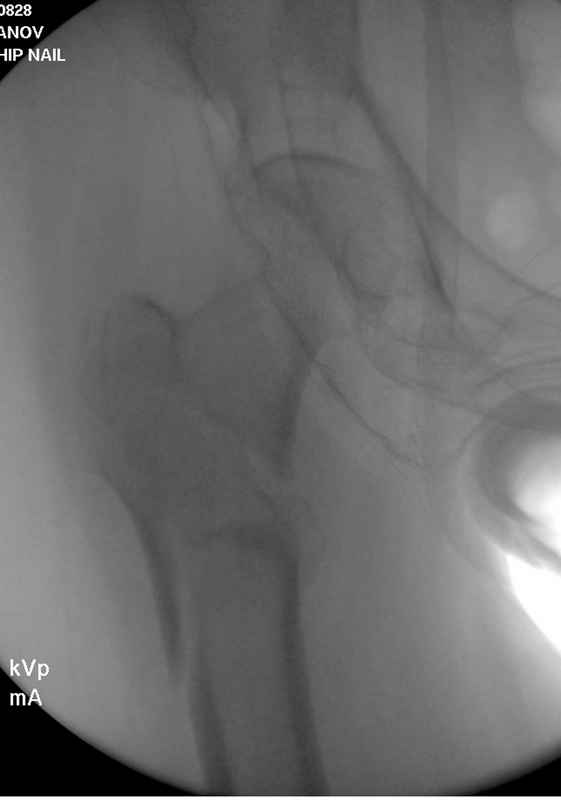

Здесь пара случаев фиксации похожих переломов:

первый высокоэнергетическая травма 36 лет

Из фиксаторов, мы бы применили цефаломедуллярные, потому что они "по закону моментов" из-за короткого рычага от центра головки к диафизу и по принципу "головка диафиз" механически лучше выдерживают нагрузки, чем пластины.

Но современные пластины с угловой стабильностью не отстают от медуллярных конструкций. Межфрагментарные шурупы и имплант как нейтрализирующее создаст адекватную фиксацию.